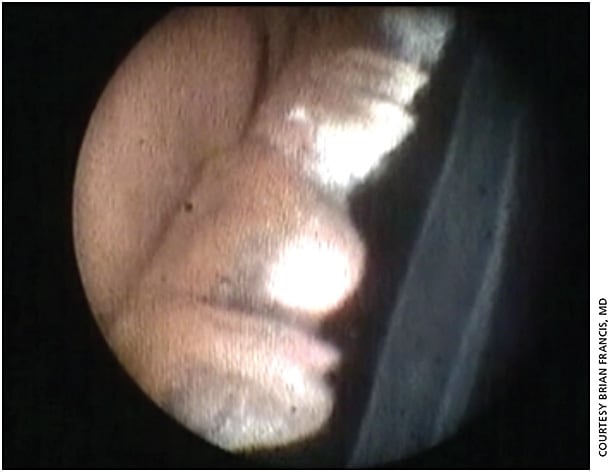

In those whose advanced glaucoma is recalcitrant to multiple glaucoma filtration surgery and other procedures, Dr. Francis recommends using ECP-plus, which uses a pars plana approach and allows laser ablation of the pars plana.

“By entering the pars plana, you’re able to view the ciliary processes … completely, and therefore you’re able to treat the ciliary processes in a more aggressive and complete manner, achieving better pressure-lowering,” he says. “You’re also treating about one or two rows of the pars plana, so that gives you even more profound pressure-lowering.” (Figure 1)

In a study published earlier this year, patients treated with ECP-plus had their mean IOP lowered by at least 61%, which was sustained for a follow-up period of more than one year. Also, patients needed fewer glaucoma medications.4